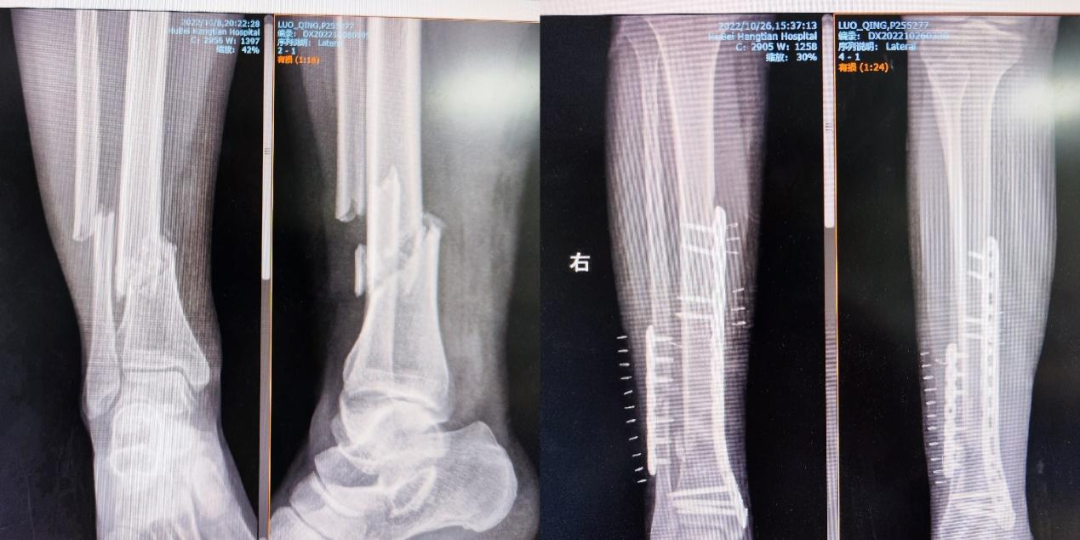

据悉,今年30岁的罗女士,因车祸外伤导致全身多处损伤伴昏迷,紧急送往湖北航天医院后医护人员积极为她完善相关检查,被诊断为颅脑损伤,颅内出血,枢椎粉碎性骨折,多发肋骨骨折,创伤性湿肺,腰椎骨折,右胫骨下段粉碎性骨折。情况危急,为尽快减轻患者痛苦及负担,骨科副主任黄华溢立即与医联体单位武汉大学中南医院的谢江涛教授取得联系,并积极组织科室多次术前讨论。

置钉偏内会压迫脊髓,会抑制患者呼吸,存在高位截瘫的风险;置钉偏外可能会波及椎动脉,出现大出血或脑供血不足的情况发生。而同时进行的还有右下肢胫腓骨复位内固定术,无疑更增加了手术难度。整个手术历时2个多小时,即便是拥有丰富手术经验的谢江涛和黄华溢也是如履薄冰、慎之又慎,在完成置钉、透视确认良好后关闭伤口,顺利完成手术。

术后两天,罗女士未出现任何神经、血管损伤的表现,四肢感觉运动良好,已经可以拄拐下地行走。